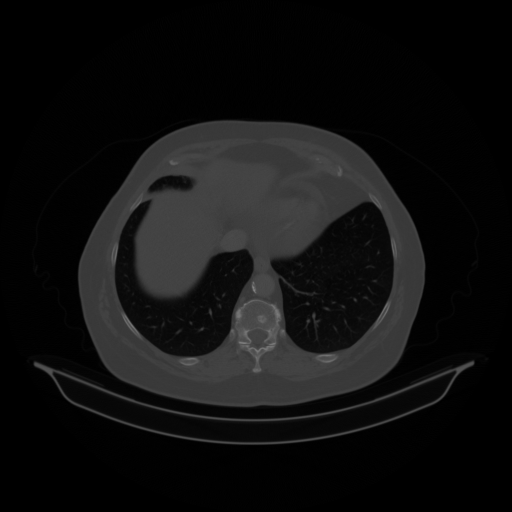

Original VENOUS CT scan

No window - Raw intensity values

Lung window (WL -600, WW 1500 β†’ Low βˆ’1350, High +150)

Mediastinum window (WL 40, WW 400 β†’ Low βˆ’160, High +240)